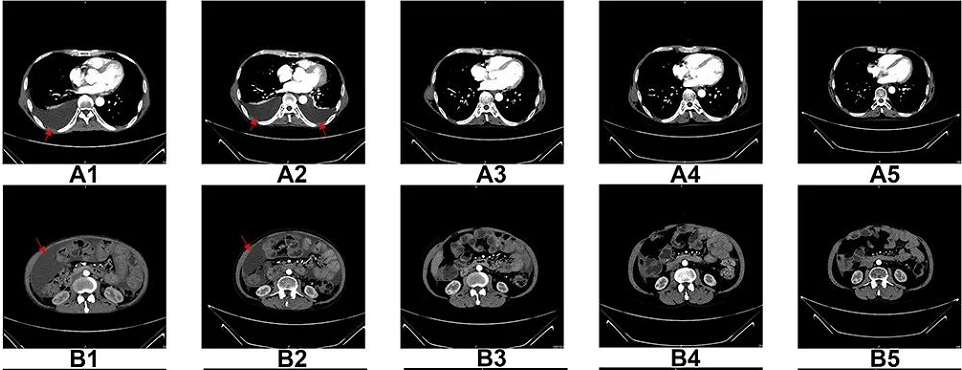

圖A1-A5:CT掃描顯示,6個療程后胸腔積液完全消失

圖B1-B5:CT掃描顯示,6個療程后腹水幾乎完全消失